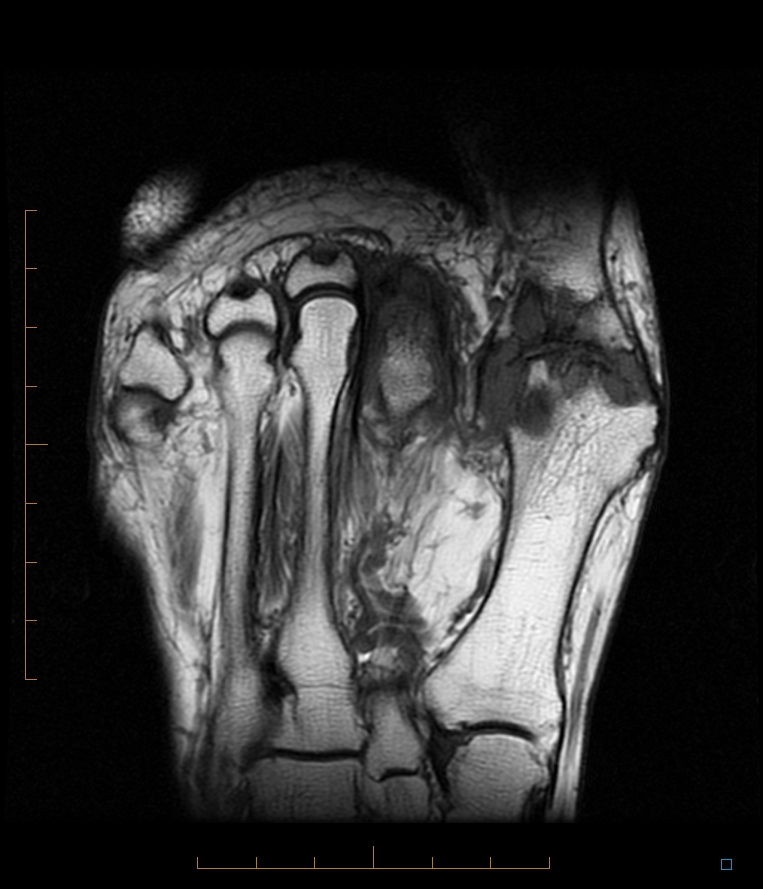

Gout 1st MTP joint Radiology at St. Vincent's University Hospital

Gout Arthritis Learning Radiology . Identify the clinical and biochemical markers of gout, including hyperuricemia and monosodium urate crystals, for accurate diagnosis. Deposition of sodium urate monohydrate crystals in synovial membranes,. Recent advances in diagnostic imaging of gout, specifically in the field of ultrasound and dect, have a great potential in helping clinicians with more accurate assessment and diagnosis of gout. There are large tophaceous deposits (white arrows) surrounding several of the joints of the right hand. Mri can demonstrate generic features of inflammatory arthritis, such as synovial thickening, effusion, bone erosions, and bone. Learn about the clinical presentation, risk factors, pathology, radiological features and treatment of acute gouty arthritis,.

Mri can demonstrate generic features of inflammatory arthritis, such as synovial thickening, effusion, bone erosions, and bone. Learn about the clinical presentation, risk factors, pathology, radiological features and treatment of acute gouty arthritis,. Recent advances in diagnostic imaging of gout, specifically in the field of ultrasound and dect, have a great potential in helping clinicians with more accurate assessment and diagnosis of gout. There are large tophaceous deposits (white arrows) surrounding several of the joints of the right hand. Identify the clinical and biochemical markers of gout, including hyperuricemia and monosodium urate crystals, for accurate diagnosis. Deposition of sodium urate monohydrate crystals in synovial membranes,.